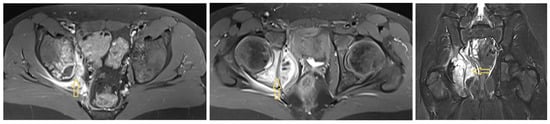

3.1.1. Patient 1

3.1.2. Patient 2

3.1.3. Patient 3